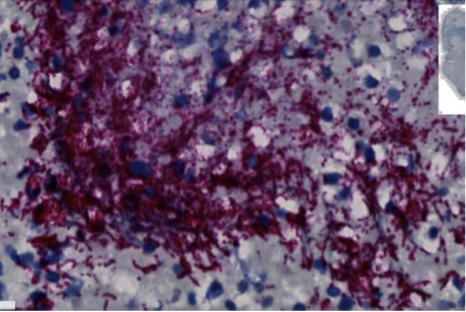

Cette bactérie du microbiote oral, retrouvée au sein de tumeurs colorectales et suspectée d’être associée à la progression du cancer, génère un intérêt grandissant. Dans une étude publiée dans Nature, des chercheurs du Fred Hutchinson Cancer Center, qui initialement voulaient savoir comment la bactérie migrait d’un site à un autre, ont mis en évidence qu’un clade très particulier est en cause, le Fusobacterium nucleatum animalis de clade 2 (Fna C2). Des résultats inattendus qui ouvrent la porte à de nouvelles modalités de prévention et de thérapeutique ciblées.

Pour ce travail, les chercheurs se sont intéressés à 135 souches de Fn : 80 issues de la cavité buccale d’individus sains et 55 issues de tumeurs colorectales venant de 51 patients. Une analyse pangénomique a identifié 485 facteurs génétiques associés au cancer colorectal. Première précision : les souches tumorales isolées appartiennent principalement à un sous-type, le Fn animalis. Deuxième découverte : il n’existe pas qu’un seul sous-type mais deux, le clade 1 (C1) et le clade 2 (C2). Et seul le clade 2 est dominant au sein des tumeurs, les scientifiques ayant même identifié 195 facteurs génétiques de Fna C2 associés à un potentiel métabolique et à une colonisation du tube digestif ; une observation confirmée dans une expérience chez la souris.

Les chercheurs ont ensuite montré qu’au sein de la tumeur de 116 patients ayant un cancer colorectal, le microbiote était enrichi en Fna C2, ce qui n’était pas le cas dans 62 prélèvements de tissus sains. Une observation retrouvée à l’analyse métagénomique du microbiote intestinal chez 627 patients ayant un cancer colorectal et 619 témoins.